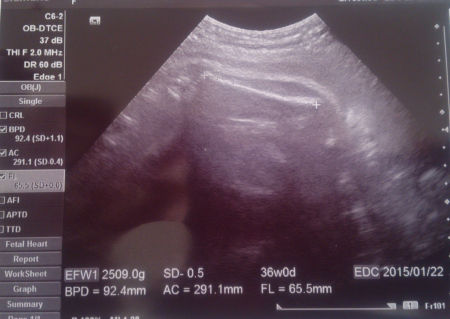

カラダのダカラ 妊娠28週から36週

妊娠35週目 胎児の体重 大きさは おむつのムーニー 公式 ユニ チャーム

妊娠37週目 胎児の体重や大きさ エコー写真 正期産へ 妊娠後期 All About

お腹の中にいる赤ちゃんの体重はどうやって計るの ハピサポ 三宅医院 産科 婦人科 不妊治療 小児科 形成外科 心理カウンセリング